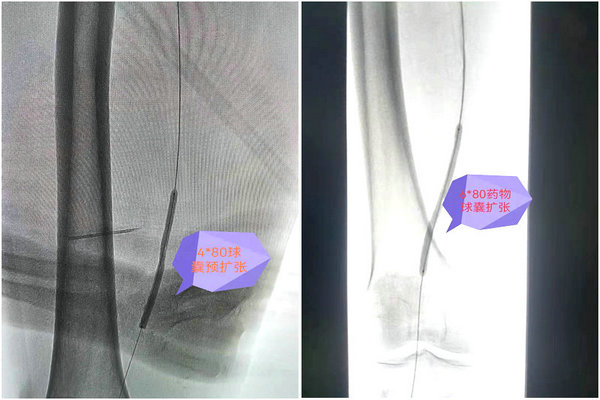

术前介入放射科马晓欧主任和杜友利医生为患者制定了详细、严谨的手术方案。术中造影见右下肢股浅动脉中下段短段闭塞,长约40mm,血流经股动脉侧支灌注至远端,利用导丝导管配合通过右下肢股浅动脉闭塞用4*80mm普通球囊预扩张,最后使用6*80mm药涂球囊快速加压贴敷3分钟,造影显示血流通畅,未见明显充盈缺损及血管夹层影像,手术十分顺利。术后第2天刘先生能够下地活动无跛行症状,患者及家属对治疗效果非常满意。(供稿:介入放射科 杜友利 编辑:宣传科 张宁)

术中影像